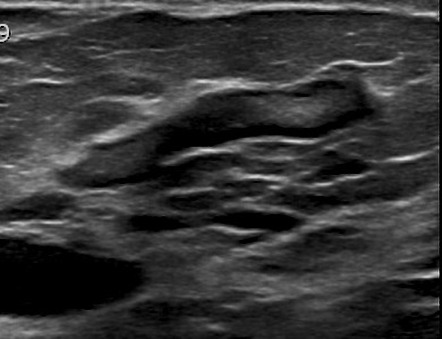

Computed tomography (ct) of the chest can detect pathology that may not show up on a conventional chest radiograph (1). Ankle fracture - Weber C (post-operative) | Image

The chest or thorax is the region between the neck and diaphragm that encloses organs, such as the heart, lungs, esophagus, trachea, and thoracic diaphragm. Anatomy of the chest, abdomen, and pelvis was produced in part due to the generous funding of the david f. 20/01/2018 · the dominant muscle in the upper chest is the pectoralis major. 15/10/2017 · radiology basics of chest ct anatomy with annotated coronal images and scrollable axial images to help medical students and junior doctors learning anatomy. Anatomy of the thorax, heart, abdomen and pelvis recommended text gray's anatomy for students. 14/09/2015 · the chest anatomy includes the pectoralis major, pectoralis minor and the serratus anterior. Find out more about the individual muscles within the chest anatomy by clicking their respective. This mri chest (thorax) axial cross sectional anatomy tool is absolutely free to use. Of the two chest muscles, the pectoralis major (a.k.a. The pec major) is the one that commands the most real estate. Other important structures, such as the pleura, only become visible when abnormal, and some are not visible at all, such as the phrenic nerve. 16/07/2019 · in addition to moving the arm and pectoral girdle, muscles of the chest and upper back work together as a group to support the vital process of breathing. Computed tomography (ct) of the chest can detect pathology that may not show up on a conventional chest radiograph (1).

This page provides an overview of the chest muscle group. The chest or thorax is the region between the neck and diaphragm that encloses organs, such as the heart, lungs, esophagus, trachea, and thoracic diaphragm. 14/09/2015 · the chest anatomy includes the pectoralis major, pectoralis minor and the serratus anterior. Anatomy of the thorax, heart, abdomen and pelvis recommended text gray's anatomy for students. Learn about each of these muscles, their locations, functional anatomy and exercises for them. The sternum is also included on a frontal view but it overlies other midline structures and so is obscured. Use the mouse scroll wheel to move the images up and down alternatively use the tiny arrows (>>) on both side of the image to move the images.>>) on both side of the image to move the images. Other important structures, such as the pleura, only become visible when abnormal, and some are not visible at all, such as the phrenic nerve. Find out more about the individual muscles within the chest anatomy by clicking their respective. Of the two chest muscles, the pectoralis major (a.k.a. Plus, how to target each to make them bigger and stronger. 15/10/2017 · radiology basics of chest ct anatomy with annotated coronal images and scrollable axial images to help medical students and junior doctors learning anatomy. Computed tomography (ct) of the chest can detect pathology that may not show up on a conventional chest radiograph (1).